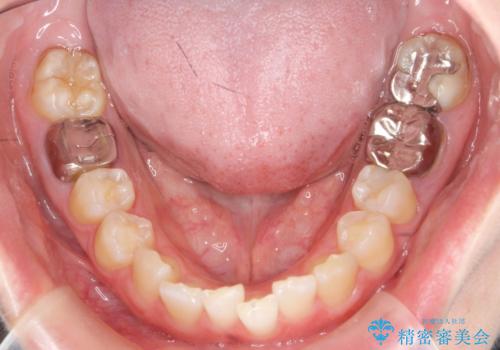

ねじれた前歯を改善するマウスピース矯正

- 大きくねじれた前歯をまっすぐに並べたい。と矯正治療を希望され来院されました。

前歯をきっちり並べるには奥歯の噛み合わせの調整を行い上下の前後的関係を治し、ねじれを取るスペースを確保していきます。

当初前歯だけ治れば良い、という心算で来院されましたが奥歯の噛み合わせも負担が大きく問題の起きやすいことをお伝えし上顎の奥歯をきっちりと後方移動行い噛み合わせの調整を行いました。・